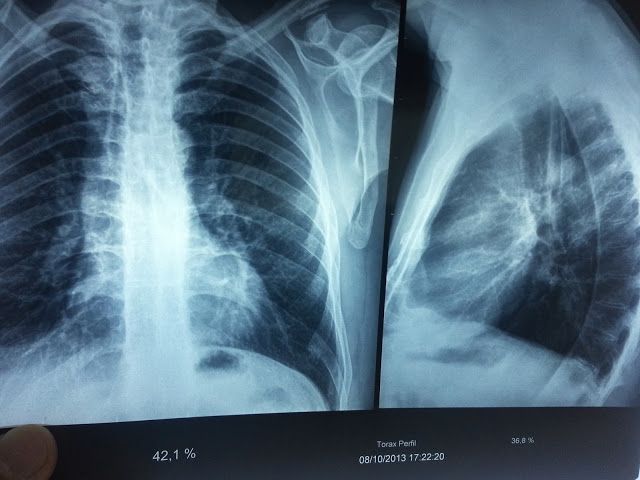

Entrenamiento de músculos respiratorios en un paciente con espondilitis anquilosante

La espondilitis anquilosante (AS) presenta manifestaciones clínicas músculoesqueléticas y cardiorrespiratorias. En ese contexto, el entrenamiento de los músculos inspiratorios (IMT) […]